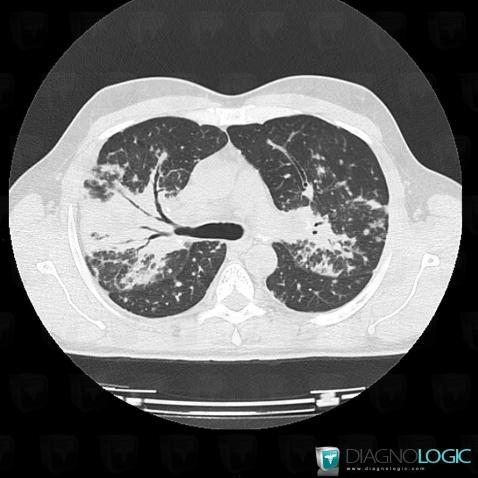

Sarcoïdose, Parenchyme pulmonaire, Scanner

Voici les informations spécifiques à l'image clé ci dessus:

- Diagnostic Sarcoïdose, Localisation(s) Parenchyme pulmonaire, comportant les gammes Maladie prédominant en péri hilaire, Condensation alvéolaire localisée, Condensation alvéolaire chronique